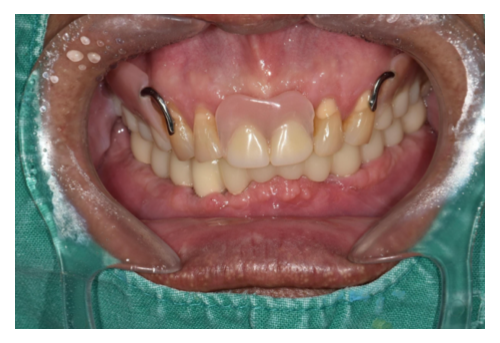

3 30대 남환 임플란트

• 경남 하동에서 고속버스타고 내원하시는 30대 남성 환자분이십니다. • 치과공포증으로 치과 방..